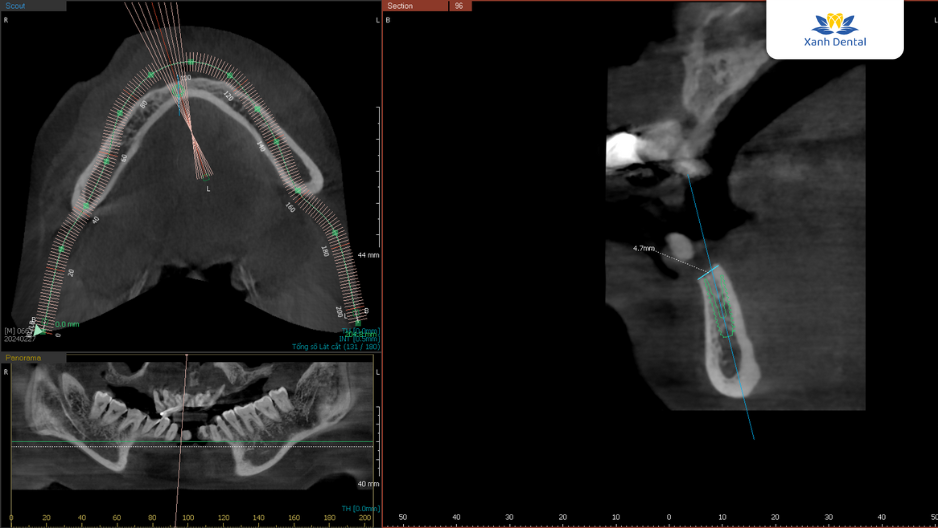

Sau khi thăm khám kỹ lưỡng và đánh giá tình trạng răng miệng của chú Sơn, Thạc sĩ, Bác sĩ Nguyễn Anh Sơn – chuyên gia cấy ghép Implant với hơn 5.000 ca điều trị thành công – đã xây dựng một phác đồ điều trị chi tiết và cá nhân hóa.

Kế hoạch cụ thể bao gồm cấy ghép toàn bộ hàm răng trên bằng phương pháp All-on-4 Implant và cấy 4 trụ Implant khôi phục lại răng cửa hàm dưới. Đây là phương pháp tiên tiến giúp thay thế chân răng đã mất bằng trụ Implant Titanium, mang lại khả năng ăn nhai và thẩm mỹ gần như răng thật. Cùng với công nghệ hiện đại, việc cấy ghép diễn ra nhẹ nhàng, không đau và đảm bảo an toàn tuyệt đối. Đặc biệt, răng sứ được phục hình trên trụ Implant có màu sắc tự nhiên, mang lại tính thẩm mỹ tối đa cho khách hàng.